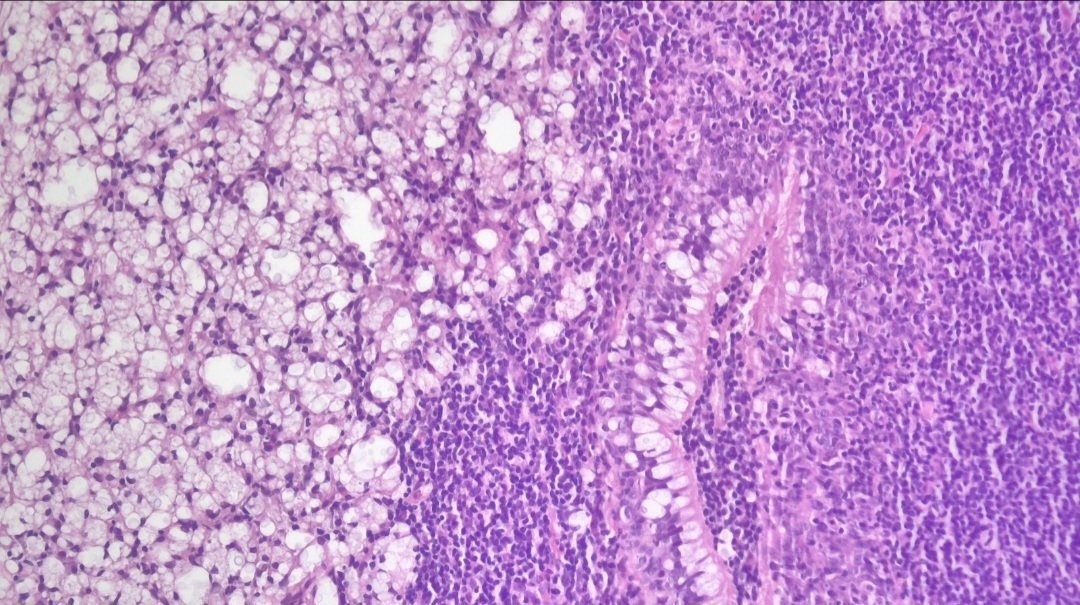

Клинический случай Пациент: мужчина 51 года, ВИЧ-положительный статус Жалобы: шум в ушах (продолжительность — 3 месяца) Данные обследования: * При оториноларингологическом осмотре выявлено: утолщение слизистой оболочки носоглотки * Выполнена биопсия Гистологическое заключение: Криптококкоз носоглотки #cryptococcus #гистология

Пациент: мужчина 51 года, ВИЧ-положительный статус

Жалобы: шум в ушах (продолжительность — 3 месяца)

* При оториноларингологическом осмотре выявлено: утолщение слизистой оболочки носоглотки

* Выполнена биопсия

Гистологическое заключение:

Криптококкоз носоглотки